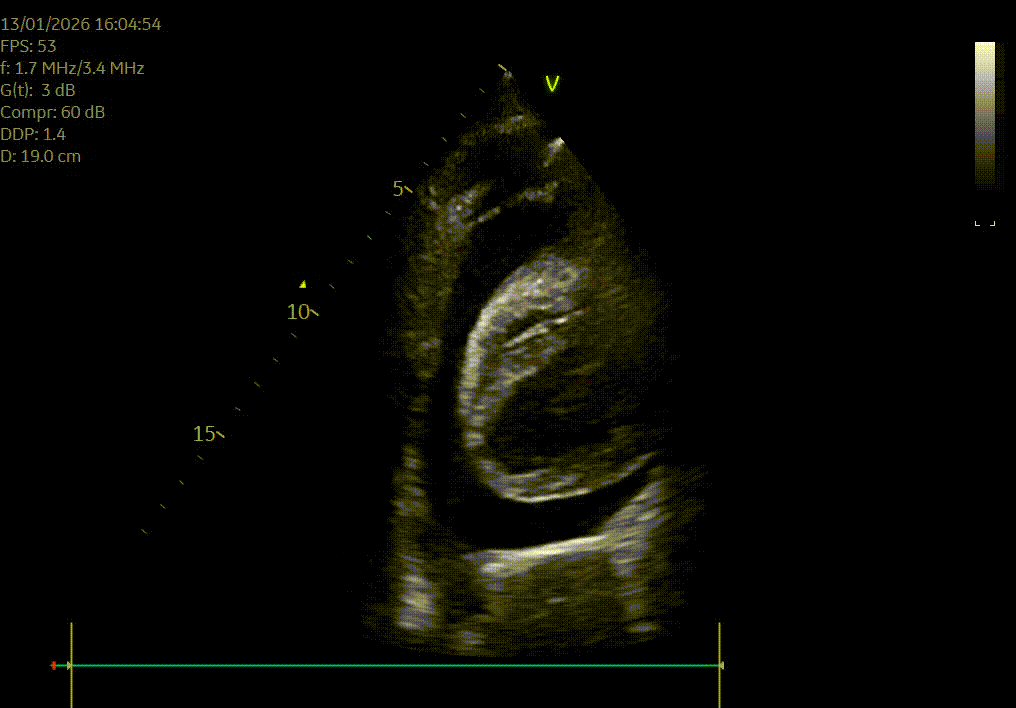

Heeft uw hond of kat een hartruis? Het is dan aangewezen om een echocardiografie (hartfilmpje) uit te laten voeren om na te gaan of er best ondersteunende hartmedicatie moet opgestart worden. Met een echocardiografie gaan we na of het hart normaal gevormd is, normaal werkt en beoordelen we de ergheidsgraad van eventuele kleplekken.

Hartonderzoek - Echocardiografie - Electrocardiografie (EKG) - Radiografie

Waarom een echografie laten uitvoeren? Echografie geeft een goed beeld van de inwendige organen zoals het hart, de longen, de maag en darmen, de milt, de lever, de galblaas, de nieren, de blaas, de baarmoeder...Met echografie is een drachtcontrole (zwangerschapscontrole) bij een kat vanaf 18-21 dagen en bij een hond vanaf 28 dagen mogelijk.

De kwaliteit van een echografie is afhankelijk van de lichaamsbouw en de mate dat je hond of kat meewerkt.